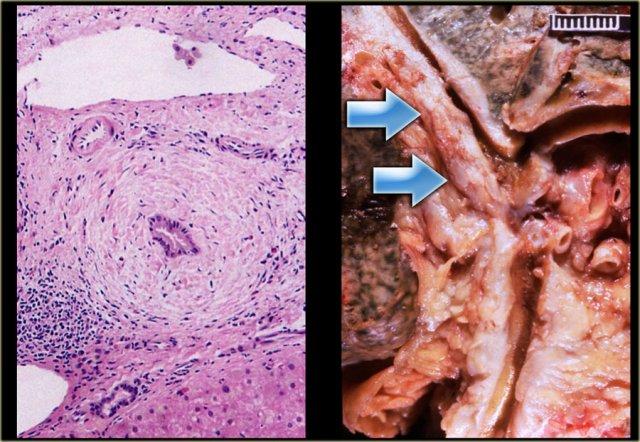

Ở ngoài cùng bên trái là tiêu bản mô học cho thấy hình ảnh viêm mạn tính xung quanh ống mật.

Tiêu bản đại thể cho thấy thành ống mật dày lên (mũi tên) gây ra nhiều chỗ hẹp.

Các chỗ hẹp trong PSC thường ngắn, khoảng 3-5 mm chiều dài, đây là điểm cần ghi nhớ vì khi tìm kiếm ung thư đường mật, các chỗ hẹp ác tính thường dài hơn 10 mm.